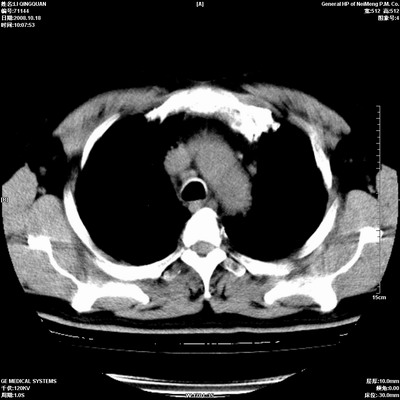

以下是引用duguo在2008-10-19 13:59:00的发言:[br]左肺上叶支气管狭窄,首先考虑中心型肺癌伴阻塞性肺炎\\肺不张.

以下是引用ybing在2008-10-19 12:58:00的发言:[br]左肺上叶阻塞性炎症-建议支气管镜进一步检查除外中央型肺癌

以下是引用随光逐影在2008-10-19 14:31:00的发言:[br]考虑左肺中央型肺癌并左肺上叶阻塞性肺炎,肺不张。